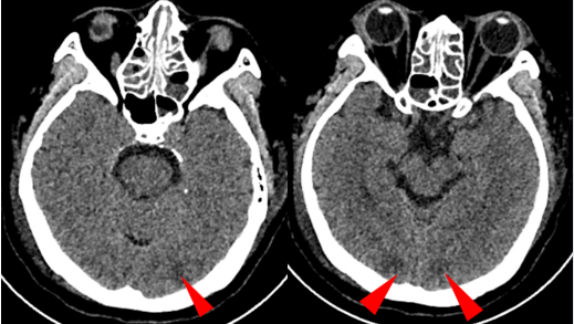

2025年7月1日,患者拔管后意识清楚,未再发抽搐、癫痫。完善头颅MRI、MRV未见异常(图2);2025年7月9日,减量激素为泼尼松40 mg qd;2025年7月11日,复查膜攻击复合物(C5b-9)水平172 ng/ml,监测HGB、PLT、LDH逐渐恢复,期间多次监测抗dsDNA、C3、C4及LA均正常;2025年7月14日,复查24小时尿蛋白1.11 g;2025年7月18日,患者病情好转出院,出院时查体:血压120~130/70~85 mmHg,心率80~90次/分,血氧饱和度99%,粗测右眼鼻侧视野缺损,余神经查体阴性(图3)。

image.png

图2 头颅MRI+MRA(2025年7月1日)